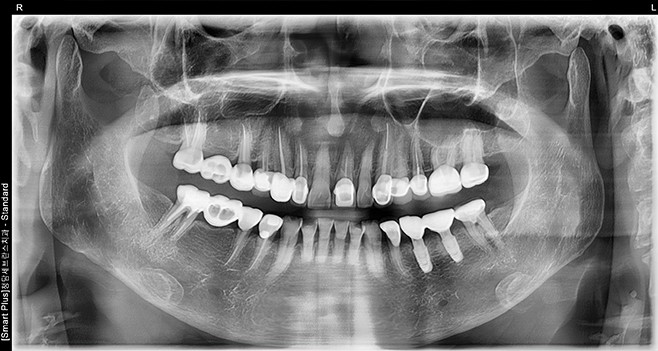

초진 파노라마